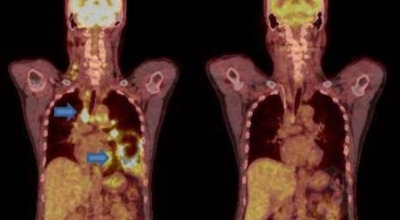

폐암은 폐에 생기는 악성 종양을 말합니다. 폐에서 직접 발생하는 원발성 폐암과, 다른 장기에서 전이되어 온 전이성 폐암으로 나눌 수 있어요. 전 세계적으로 매년 약 130만 명이 폐암으로 사망하는데, 이는 암으로 인한 사망 원인 중 가장 높은 비중을 차지하고 있습니다.